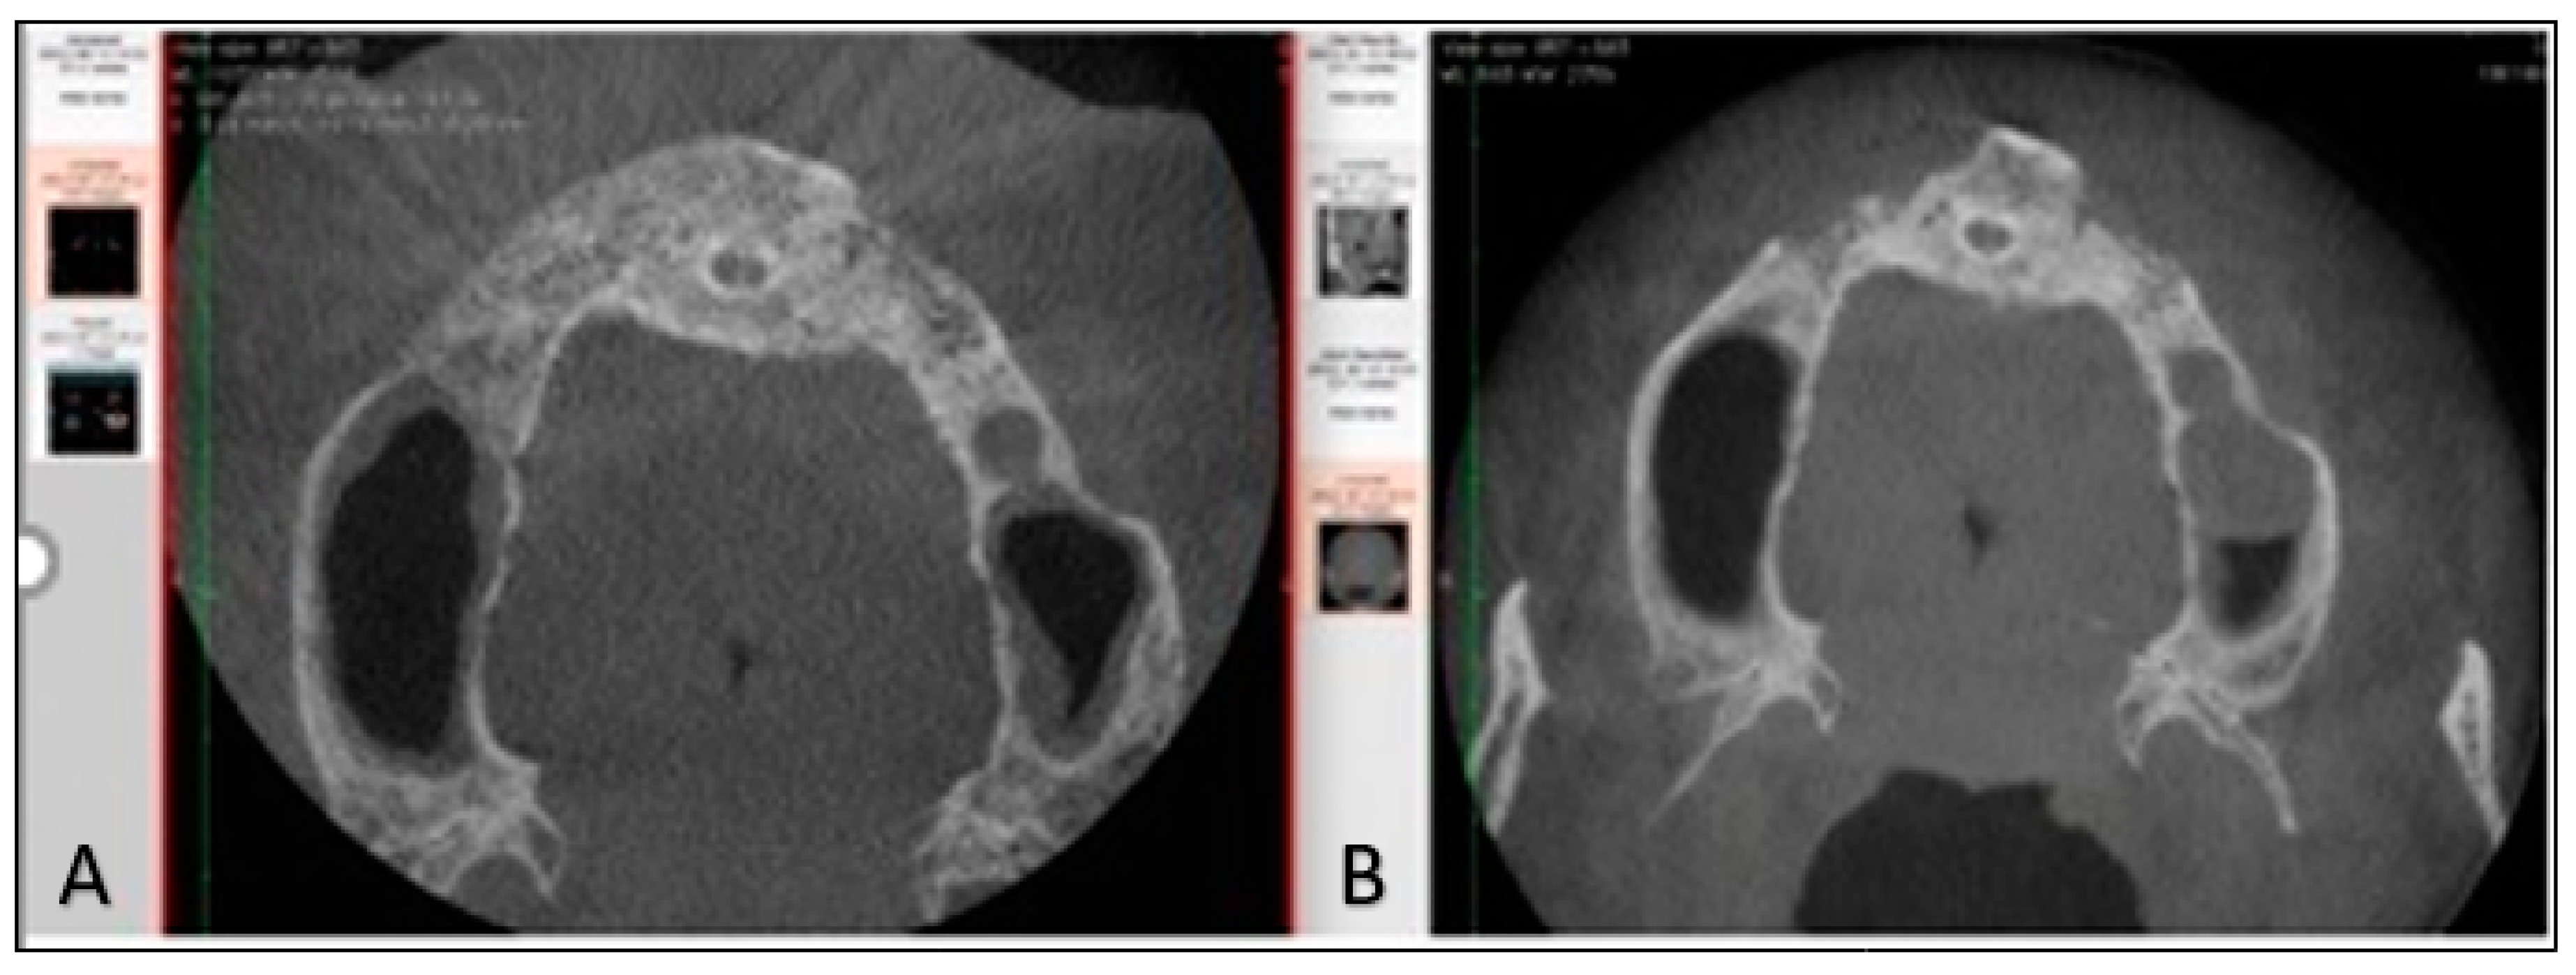

2. Case Report

2.2. Surgical Phase